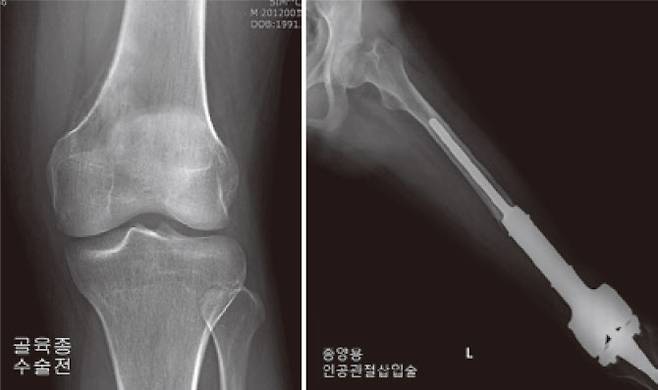

반면에 육종이 확진되면 수술적 치료는 필수다. 과거에는 육종암이 사지에 발생하면 해당 부위를 대부분 절단해 치료했다. 하지만 1970년대 항암 및 방사선 치료를 보조적으로 사용하게 되면서 요즘은 절단까지 시행하는 사례는 5% 미만으로 알려져있다. 현재 대부분 수술은 종양을 제거하면서도 사지 기능은 최대한 살리되 생존율을 높이는 ‘사지구제술’을 시행하고 있다.

사지구제술은 먼저 암세포 병변을 광범위하게 절제하고, 결손된 뼈와 연부 조직을 재건하는 순서로 진행한다. 재건이란 말 그대로 결손된 구조물을 대치물로 채워 넣는 방법이다. 금속으로 만들어진 인공관절을 삽입할 수도 있고, 또는 자신의 뼈를 재이용하는 자가골 이식, 다른 사람의 뼈를 이용하는 동종골 이식 등의 방법이 있다. 최근에는 3D 프린팅을 이용해 자기 뼈에 최적화된 대치물을 제작해 넣는 수술이 새롭게 각광 받고 있다.